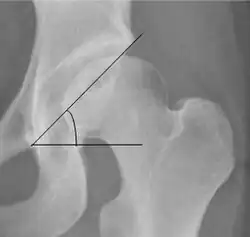

Center-edge angle of Wiberg

The superior-lateral coverage of the femoral head.

• >20° (<55 years old)[notes 2]

• <24° (>55 years old)[notes 2]

• >40° indicates overcoverage